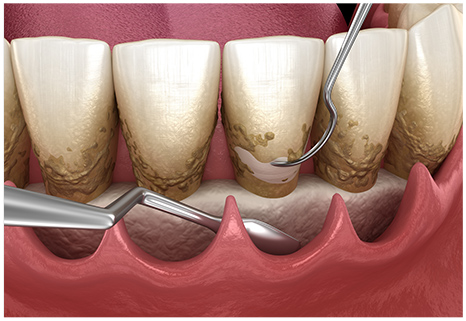

スケーラーという器具を使用し、歯面に沈着したプラークや歯石などを除去します。

特殊な器具を使用してスケーリングでは取り除けない歯周ポケット内部や歯根に付着している歯垢や歯石の除去を行います。